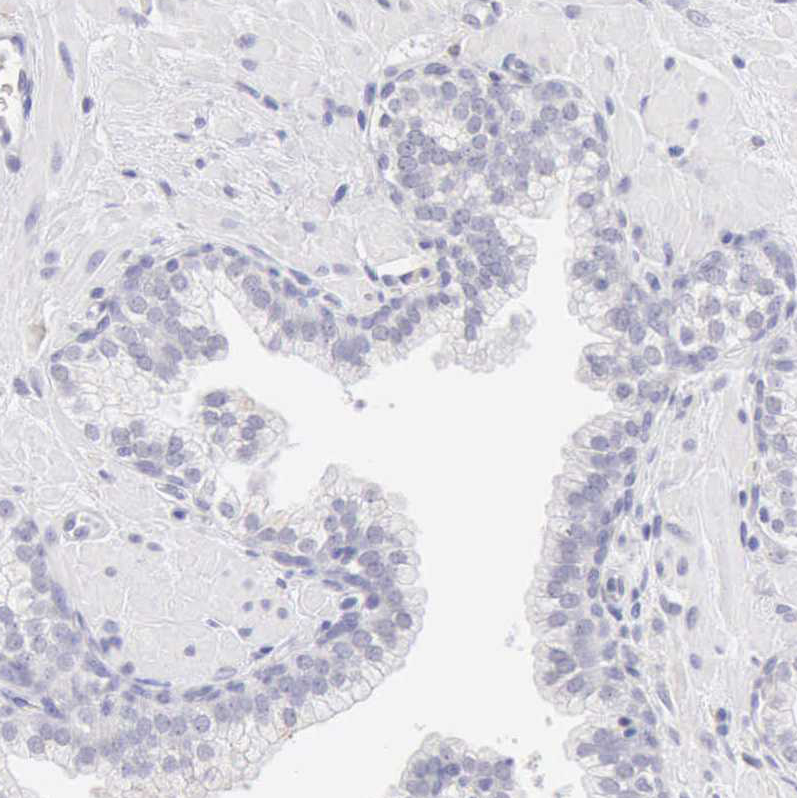

Immunohistochemistry analysis in human pancreas and prostate tissues using HPA001140 antibody. Corresponding RNASE1 RNA-seq data are presented for the same tissues.